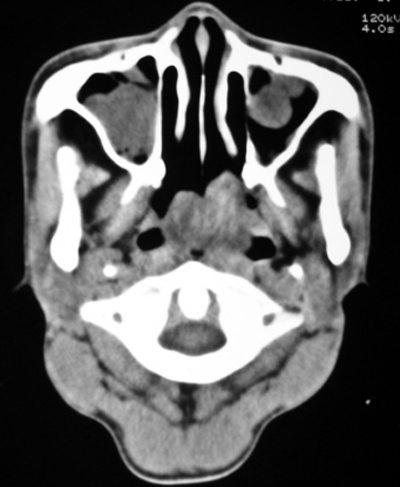

以下是引用bmw011在2009-4-23 13:23:00的发言:[br]考虑鼻息肉,上颌窦、筛窦炎

以下是引用syfszcw在2009-4-23 13:21:00的发言:[br]双侧上颌窦 筛窦慢性炎症,鼻息肉 会厌ca[br][br][本贴已被 syfszcw 于 2009-4-23 13:36:46 修改过]

以下是引用随光逐影在2009-4-23 19:35:00的发言:[br]1)鼻咽、口咽、左侧鼻腔及右侧鼻后孔处新生物,考虑息肉可能性大。2)双侧上颌窦及双侧筛窦炎症,不排除双侧上颌窦内息肉可能。